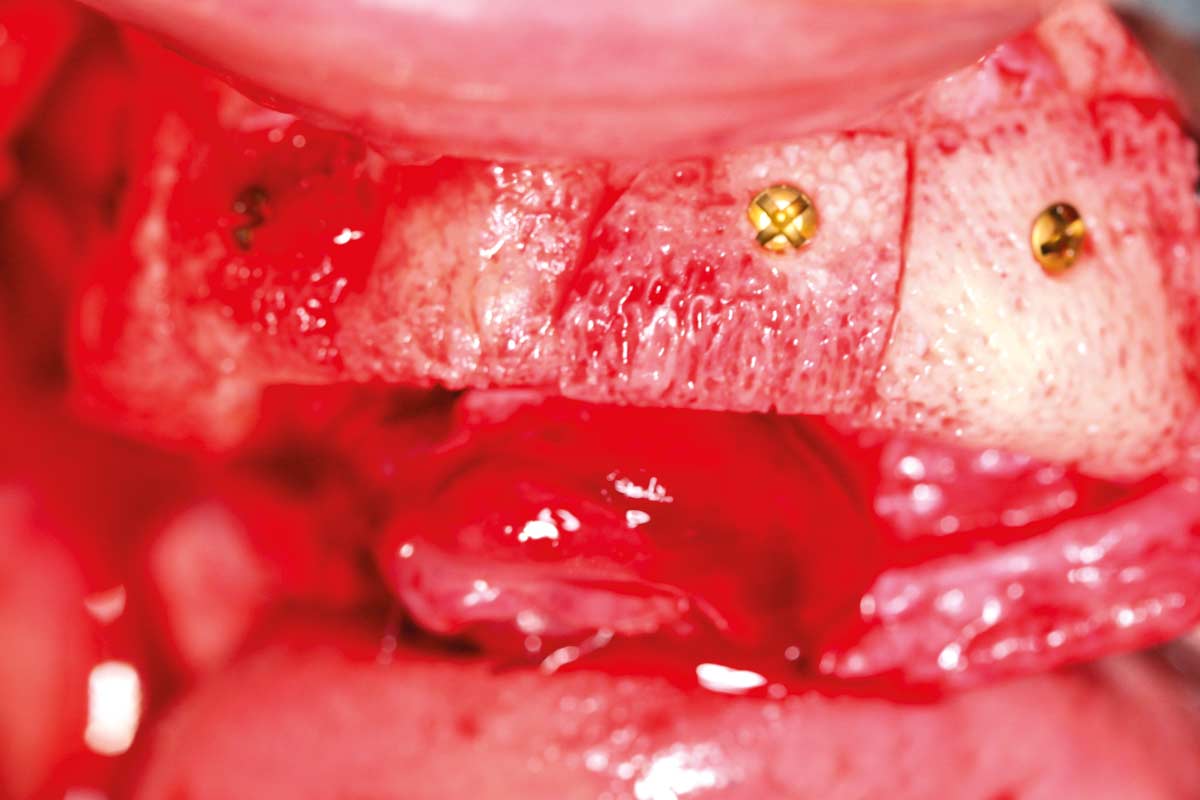

Preoperative situation – Maxillary defect in area 14-16 (loss of implant 16 due to periimplantitis, tooth 14 extracted recently and area 15 already edentulous for a while)